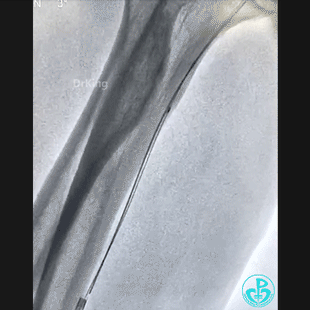

穿刺导丝掉进桡动脉,已经完全出了动脉鞘外。

先是从桡动脉鞘进抓捕器没有抓捕成功,后来从股动脉进抓捕器也没有抓捕成功。

桡动脉鞘进JR 4.0指引导管,送入Sion,沿Sion送入2.5mm球囊,球囊越过穿刺导丝到达远端,6atm“打起来”后回撤,导丝被球囊带回来到指引导管口附近。